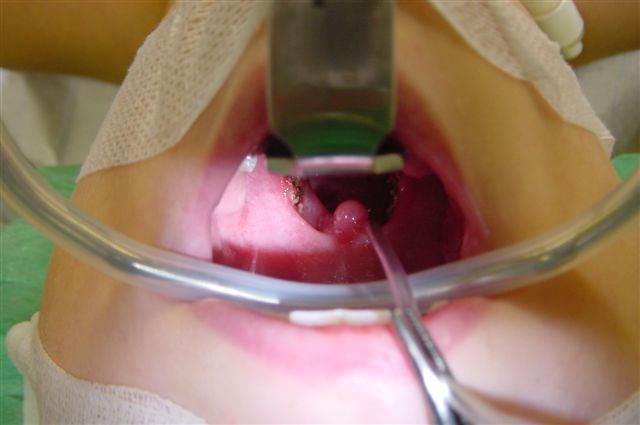

Als besonders schonend hat sich der Diodenlaser bei dieser Operation erwiesen. Dabei wird mit dem Laser blutungsfrei der mittlere Anteil der vergrößerten Gaumenmandeln beidseits entfernt. Auf diese Weise wird wieder mehr Platz im Rachenraum geschaffen. Der äußere Anteil der Gaumenmandeln bleibt vollständig erhalten und damit auch das für das Immunsystem wichtige aktive Mandelgewebe. Es handelt sich hierbei nicht um eine Entfernung der Mandeln.

| vergrößerte Mandeln | Operation | Laserwirkung |